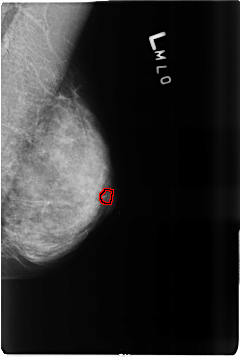

B_3516_1.LEFT_MLO

FILE: B_3516_1.LEFT_MLO.OVERLAY

TOTAL_ABNORMALITIES 1

ABNORMALITY 1

LESION_TYPE CALCIFICATION TYPE PLEOMORPHIC DISTRIBUTION CLUSTERED

ASSESSMENT 4

SUBTLETY 3

PATHOLOGY MALIGNANT

TOTAL_OUTLINES 1

BOUNDARY